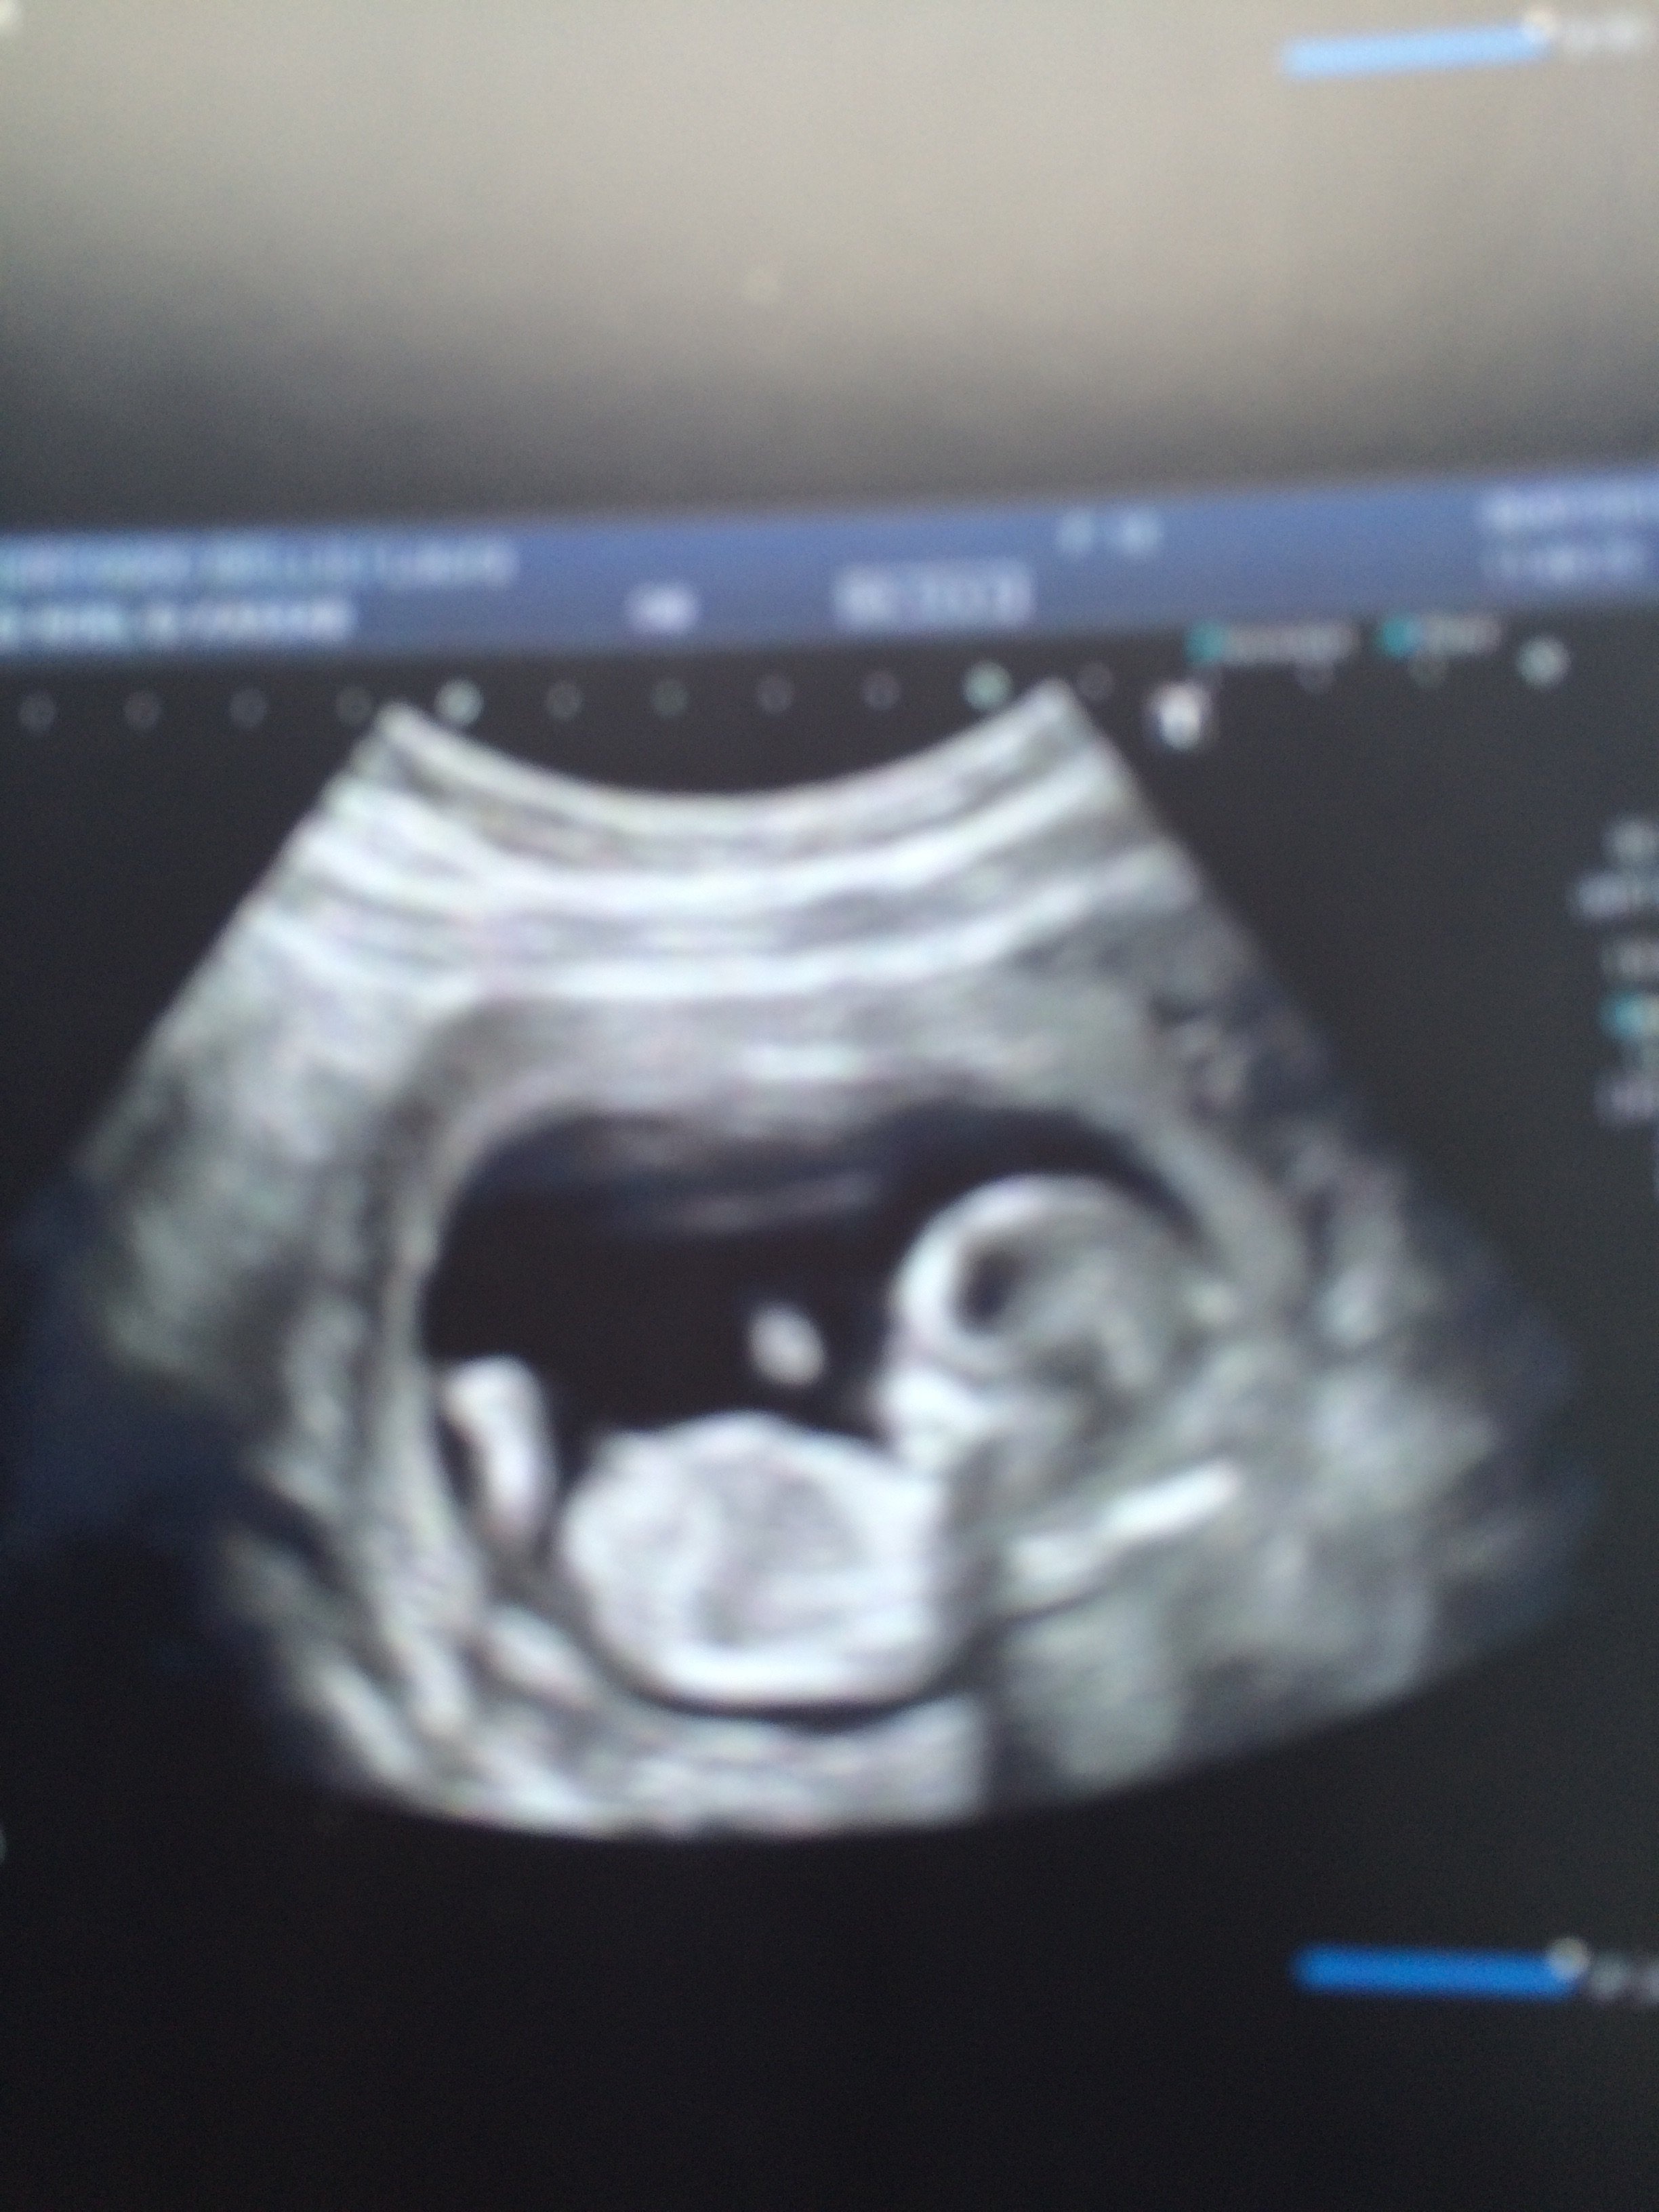

Bon j'ai recuperer les photos de l'echo ::

image.jpg

Voila conclusion : pas d'anomalie detectés

Alors tout est ok! Col bien fermer, mesure de l'echographie nickel.